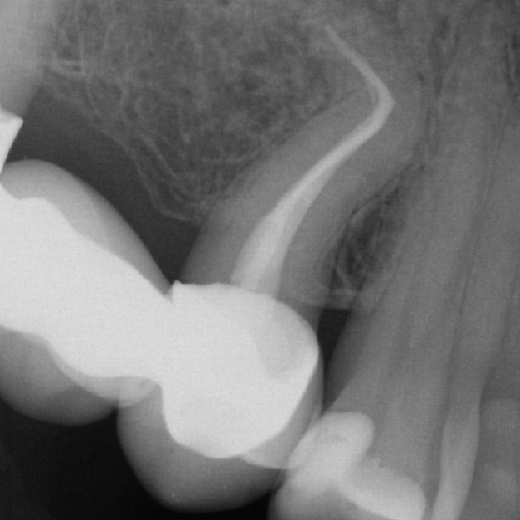

Fallbeispiel: Zahn 15 mit starker Krümmung

Jeder Zahn ist einzigartig – in diesem Fall zeigte sich Zahn 15 mit einer starke Wurzelkrümmung. Trotz der starken Krümmung konnte eine Wurzelkanalbehandlung durchgeführt werden und somit auch die Brücke erhalten werden.